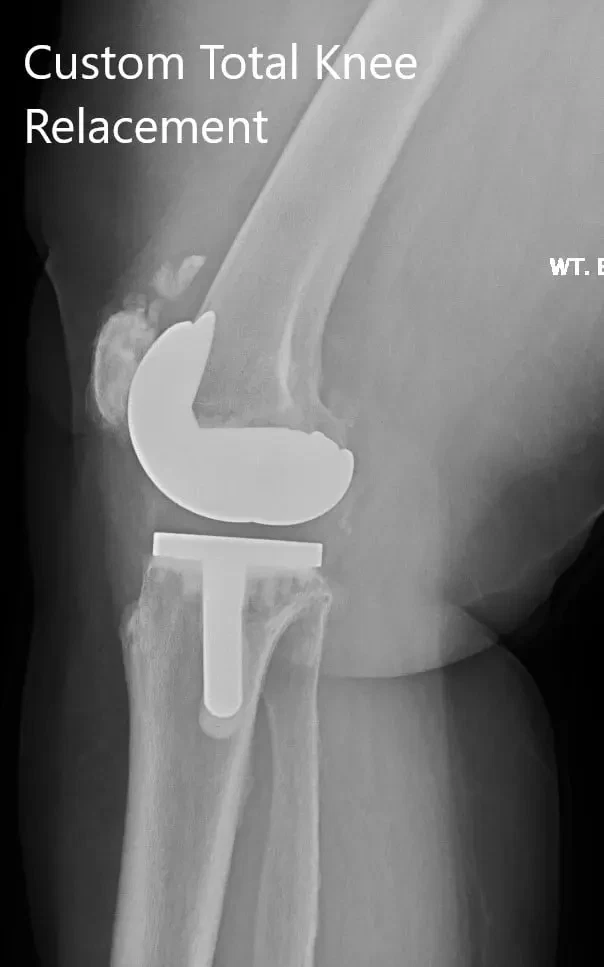

Postoperative X-ray showing the AP view of both knees

Postoperative X-ray showing the lateral views of both knees.